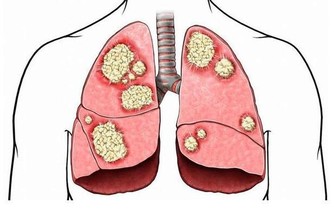

1. 肌肉痙攣

當人體處在缺水狀態時,肌肉無法有效地接受大腦所傳輸的神經信號;腿部肌肉發生這類情況的概率更高,表現症狀便是小腿或大腿抽筋。鍛煉強度過高,沒有及時補充水分時,肌肉中還會出現電解質失衡的情況。如此一來不僅會導致肌肉痙攣,還會增加鍛煉之後出現肌肉酸痛的風險。